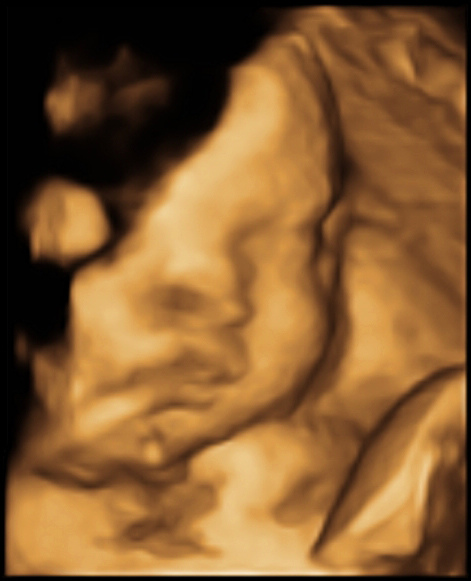

2015/10/14 小星星三十九週

其實是15號39週, 雖然醫生說我們等著生就可以了, 不一定要再回診